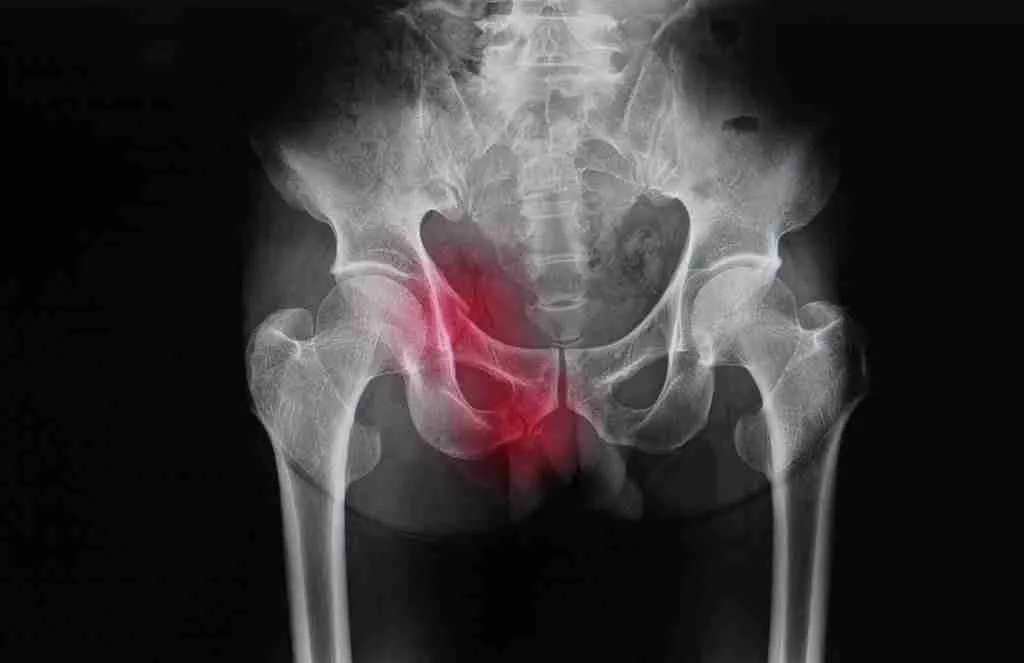

Total hip arthroplasties are one of the most common and most successful surgeries of our time. A new hip joint can decrease your pain and give you your life back. But of course, there is still the risk of a painful hip replacement.

Nearly 96% of people who undergo hip replacement surgery report complete satisfaction, even 16 years after surgery! A smaller number of people, ranging from 12% up to 18% (depending on what study you look at), have continued pain. In most cases, it is linked to the femoral component (the stem that is placed in your upper thigh bone). But there are several reasons why one may still experience pain after a total hip arthroplasty. Let’s take a look at some of the most common causes.

Without warning, patients can begin to note pain in their hip, thigh, or even pelvis. Unfortunately, these fractures can occur at sites away from the replacement site, such as into the pubic ramus or other parts of the pelvis due to the changes in stress and load that comes with the newly replaced hip.